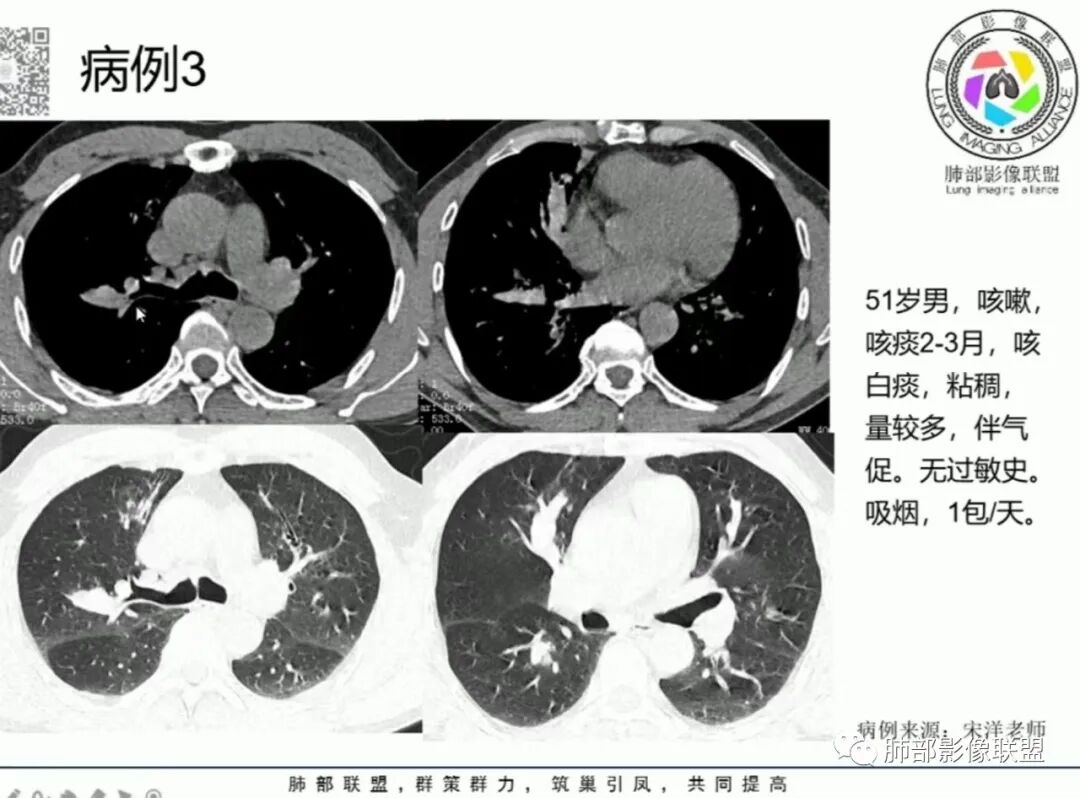

1.中年女性,主因“咳嗽、咳痰半年余”入院,既往史:8年前因左肺病在外院变行左肺叶切除术,诉术后抗结核治疗1年,具体病理等不详。实验室IGE显著增高。

2.胸部CT:右肺上叶及中叶不规则块状影,沿支气管走行方向指套样影,支气阻塞湖嵌塞,腔内可见高密度影。灶周可见磨玻璃,外围见结节影及树芽征。左肺体积缩小,见不规则条索影、胸膜增厚,纵隔牵拉左移。

3.综合分析:结合患者病史及胸部CT主要鉴别ABPA(右肺上叶不规则块影,指套样顺延支气管方向,抗结核治疗1年,肺部病灶仍明显)及继发性肺结核TB(右肺上叶不规则肿块,其可见高密影,边缘模糊,周围卫星灶、树芽征,沿支气管爬行)。

完善气管镜及病理、检验结果(IgE显著增高)等支持ABPA诊断。且给予激素及伊曲康唑治疗后复查胸部CT提示病灶较前吸收,所以诊断明确。

胸部影像学的特异性改变:随着胸部高分辨率CT(HRCT)的普及,ABPA常见肺部影像表现包括黏液嵌塞、支气管扩张、小叶中心性结节、树芽征和马赛克征等。根据是否有中心性支气管扩张,ABPA可分为变态反应性支气管肺曲霉病-血清IgE增高型(ABPA-S)和变态反应性支气管肺曲霉病-中心性支气管扩张型(ABPA-CB)。气道黏液嵌塞在ABPA很常见,胸部HRCT上表现为指套征或牙膏征。气道黏液栓通常为低密度影,但20%也可为高密度黏液影(high-attenuation mucus,HAM),定义为气道内黏液栓密度高于脊柱旁肌肉的 HRCT值,这也成为ABPA特征性的影像表现之一,外周细支气管黏液阻塞可见“树芽征”。中央性支气管扩张曾一直是ABPA诊断标准之一,但其用于诊断ABPA的敏感度仅为37%。此外,33%~43%的中央性支气管扩张也可延伸至外周,26%~39%的ABPA只有周围性支气管扩张。因此,目前认为中央性支气管扩张应视为ABPA的并发症,而非其诊断标准。